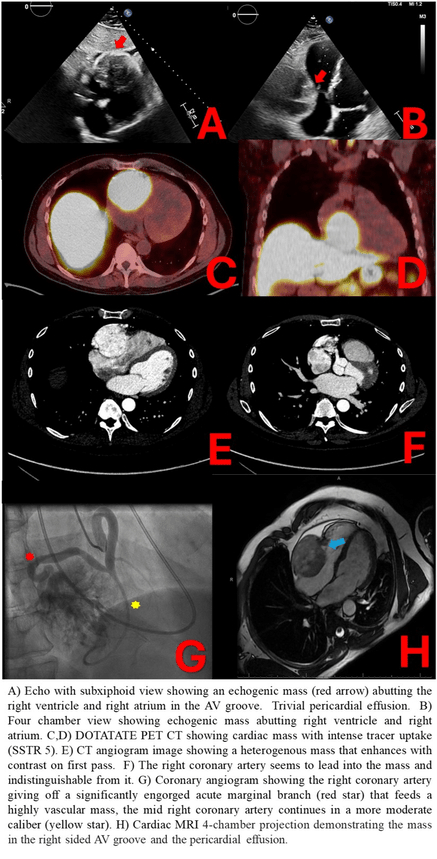

A TTE showed a 5.7 x 5.9 cm echogenic mass pushing against the RV and RA. Prospective ECG-gated CT scan of the chest revealed a highly vascular intrapericardial mass (6.0 x 7.7 mm) anterior to the RA and RV with the RCA leading into it. Cardiac MRI showed a large, circumscribed mass moving within the RV-free wall without evidence of depressed RV ejection fraction or significant coronary artery compression. Coronary angiogram found an engorged acute marginal branch feeding the highly vascular mass and the RCA continuing under the mass to give off a small PDA and a small RPL. There were normal filling pressures and no significant obstructive CAD. A multidisciplinary team determined a high concern for cardiac paraganglioma. Serological workup was notable for elevated serum epinephrine (335 pmol/L). 24-hour urinary dopamine was elevated (831.5 ug/TV) while 24-hour urinary catecholamines/metanephrines were normal. A DOTATATE PET/CT scan confirmed presence of a cardiac paraganglioma. Genetic workup did not reveal presence of any succinate dehydrogenase (SDH) mutations.